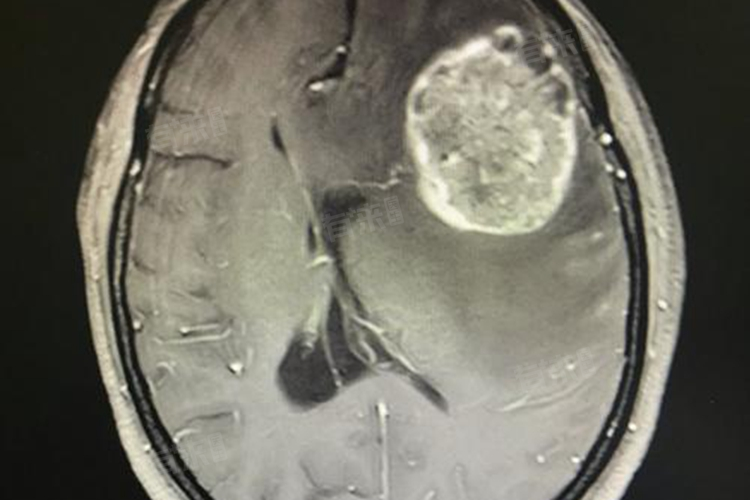

肺癌扩散到脑部,即发生脑转移,是肺癌晚期的严重并发症,并不意味着患者无药可救或治疗无望。随着医疗技术的不断进步,肺癌脑转移患者的治疗方法和生存机会都在不断增加。

- 除了上述治疗方法外,手术治疗也是一种可行的选择。对于转移病灶较小、位置较局限的患者,可以在医生操作下将癌症扩散到头部的病变组织进行外科手术切除,但手术治疗多数需要结合其他治疗方式,以更好地提高患者生存率。

肺癌脑转移患者的生存期还受到多种因素的影响,包括转移灶的大小、数量、位置、是否伴有其他并发症等。因此,经过规范的全身治疗、颅脑放疗、靶向治疗等综合治疗手段,患者的中位生存期可延长至10-12个月,甚至部分患者能达到3-5年或更长的生存期。